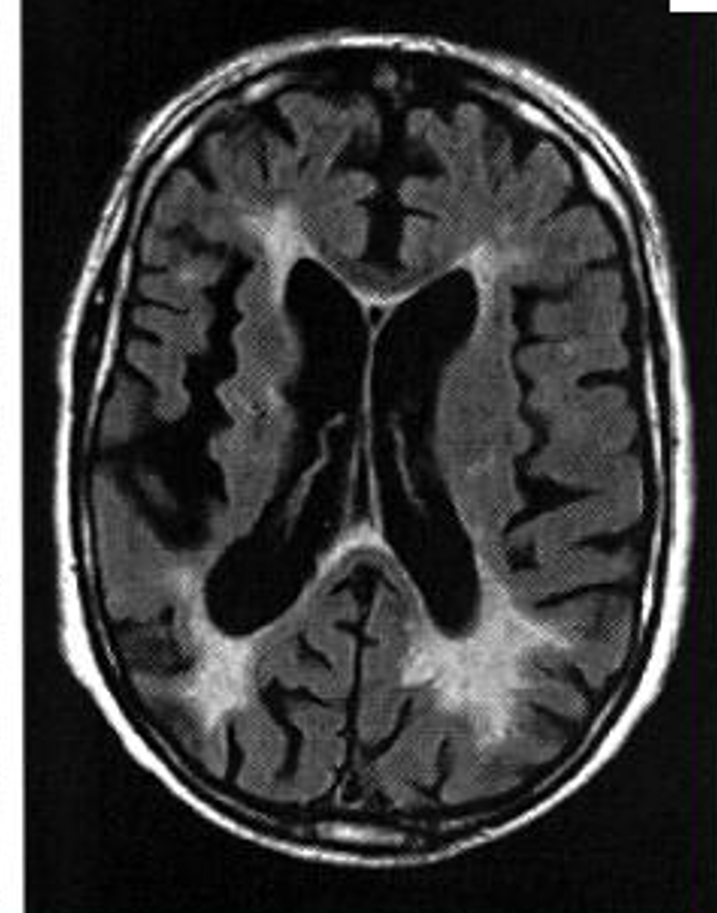

Quelle est la séquence de cette IRM? Quel diagnostic et pourquoi?

IRM séquence T2

HPN car dilatation tétra-ventriculaire, plage hyposignal T2 autour, et atrophie corticale modérée